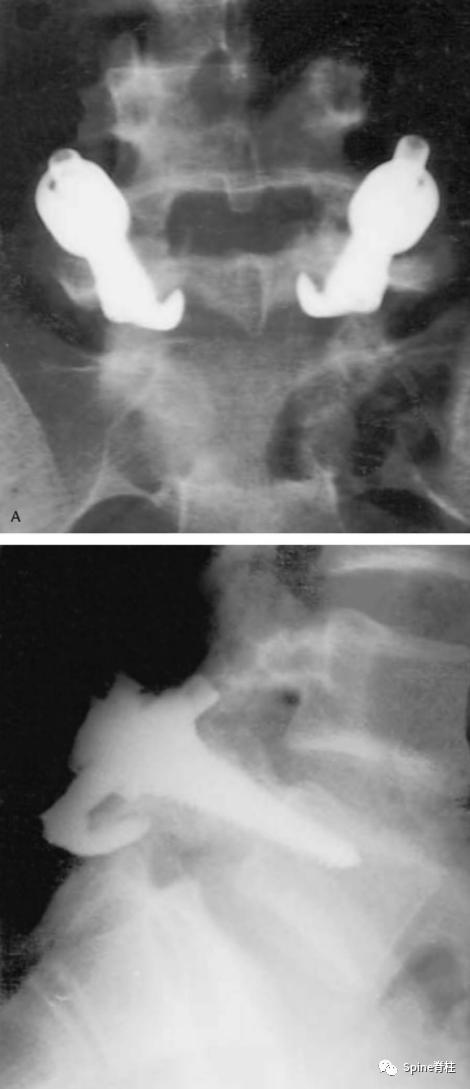

诊断腰椎峡部裂,腰椎双斜位片通常是需要的,表现为“苏格兰狗脖子”断了(见下图)。但对于一些隐匿的患者,腰椎双斜位片是看不出的,这时候需要行腰椎CT、MRI进一步明确诊断,少数部分需行核素骨扫描才能明确诊断。

腰椎峡部在腰椎斜位片上常比喻为苏格兰狗(Scotty dog)的脖子

椎弓崩裂征象:X线腰椎45°斜位摄片示上关节突轮廓似"狗耳",横突似“狗头/嘴”,椎弓根似“狗眼”,下关节突似“狗前肢”,关节突肩部或称峡部似“狗颈部”。椎弓峡部崩裂时,“狗颈部”可见裂隙。

腰椎斜位片上的苏格兰狗和断裂的脖子(峡部裂)